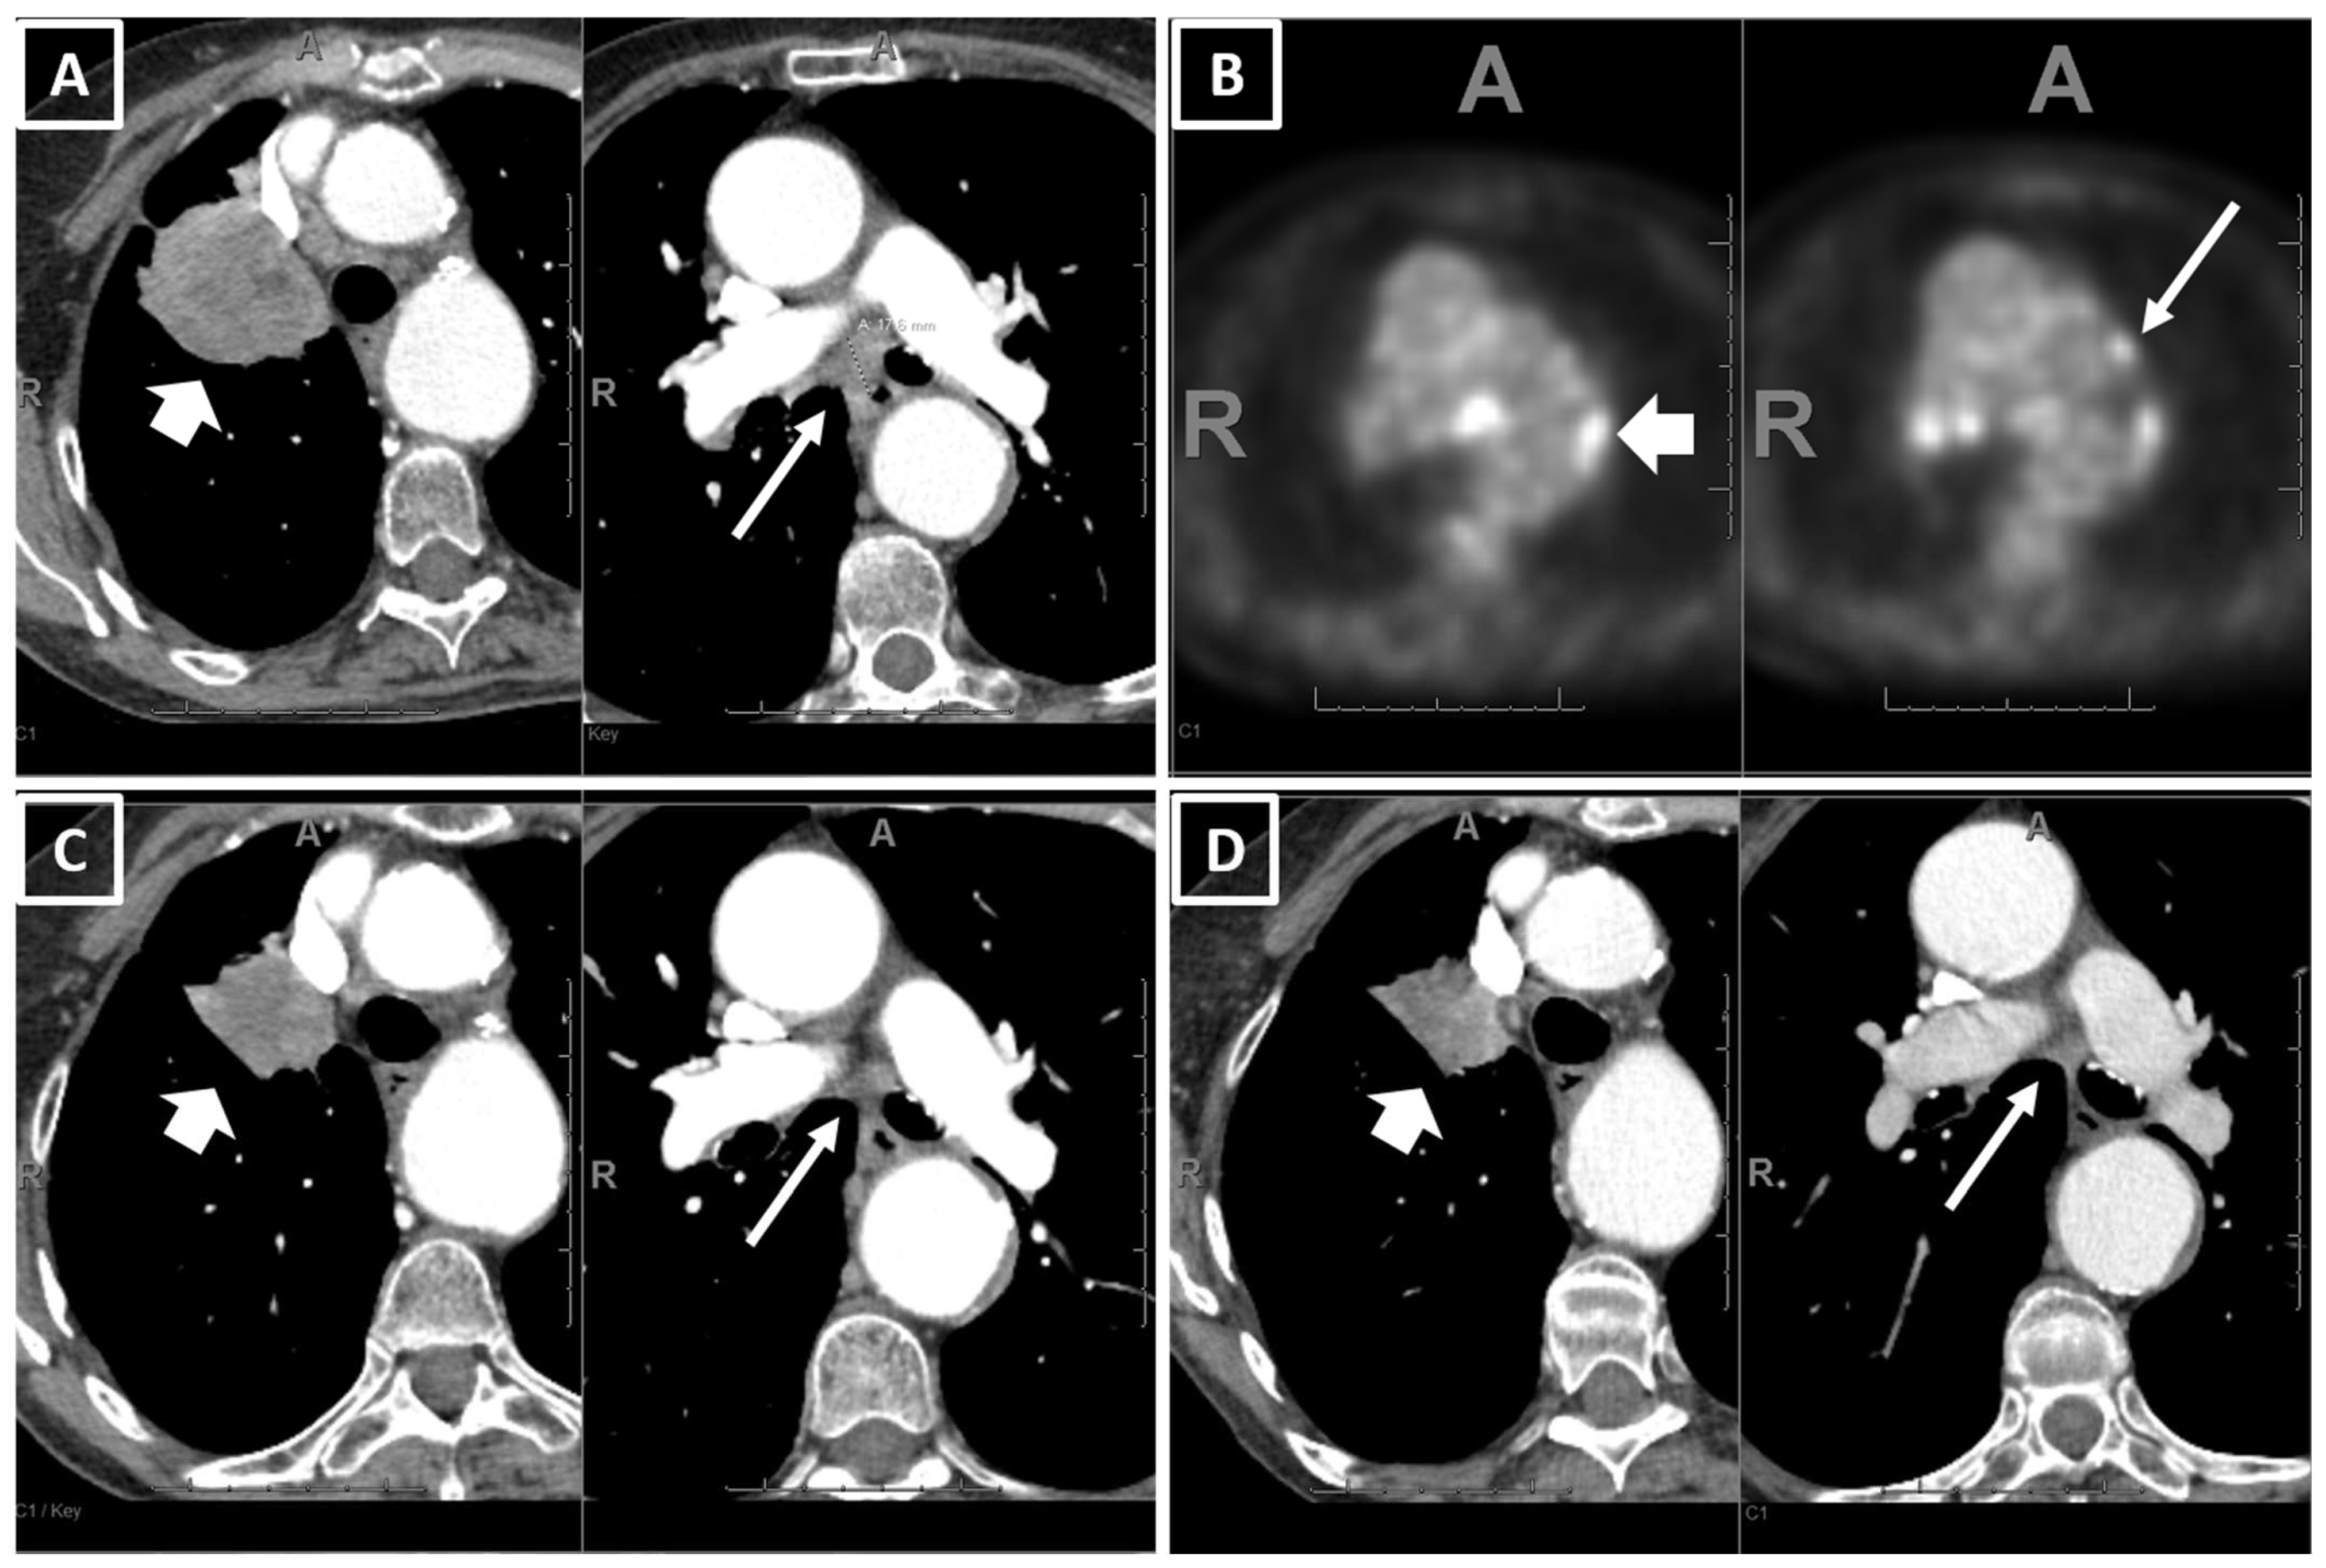

2.2. CT Scan Acquisition and Review

| On baseline CT: Number of patients with metastatic involvement in organs (n, col%) | |||||||

| 3 | 2–4 | 3 | 2–4 | 2 | 2–3 | 0.0015 * | |

| No. of involved organs on baseline CT | ||||||||

| 1.67 | [1.27 | 2.27] | 0.0004 | 1.59 | [1.19 | 2.20] | 0.0027 | |